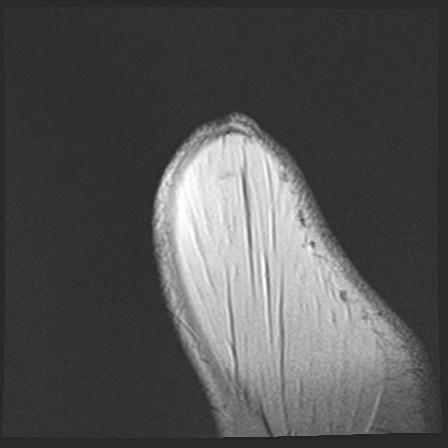

60058 3/9 11/4 右肩 2R+MRI 73歳男性 肩腱板損傷